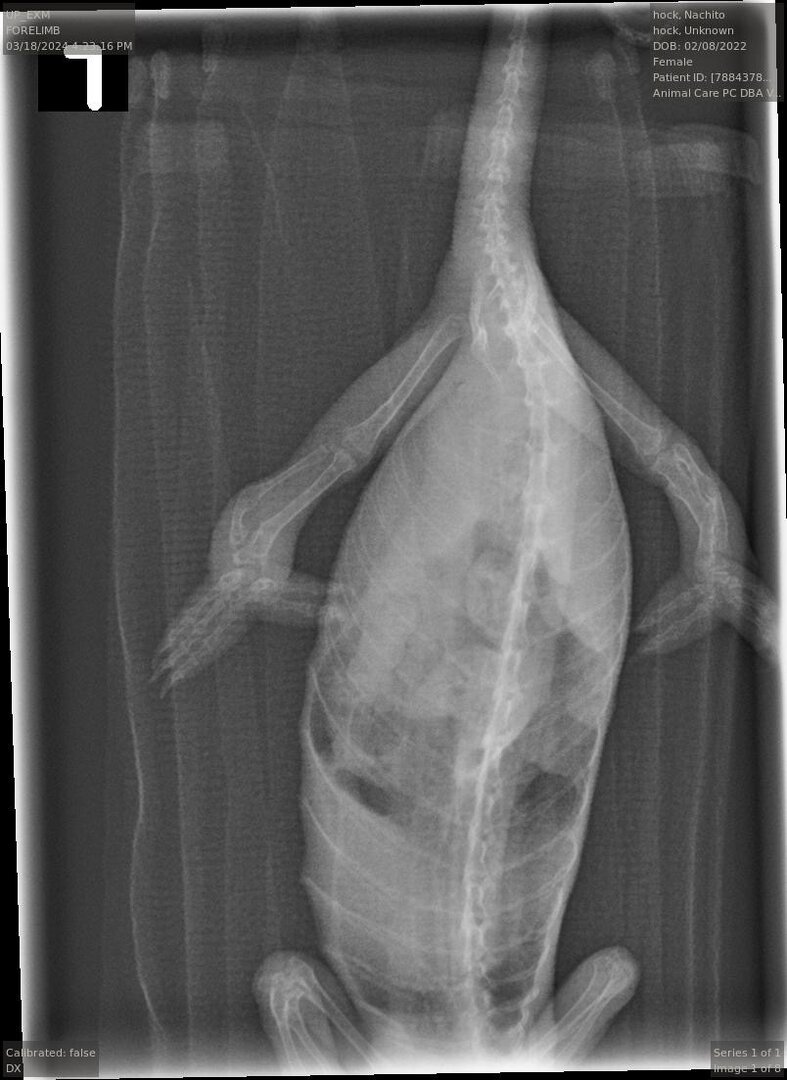

! But today at a vet appointment, Nachito was finally diagnosed with gout. After months of her uric acid levels seeming to be normal, today they came back as elevated.

Other than the uric acid levels and pore, the vet said there was nothing else significant on the X-rays and ultrasound.

Anyway! I’m hoping to get an email of the X-rays to share! If anyone has any more advice on gout or anything similar, it is welcome! Thanks for all the support as always!